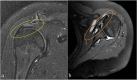

The rotator cuff is a group of four muscles and tendons surrounding the shoulder joint providing it strength and stability. The rotator cuff consists of the subscapularis, supraspinatus, infraspinatus and teres minor. Many shoulder complaints are caused by rotator cuff pathology such as impingement syndrome, tendon tears and other diseases e.g. calcific tendonitis. Diagnosis starts with clinical history and physical examination, after which imaging is often used to help confirm clinical findings depending on the differential diagnosis. The aim of the article is to review the frequently used imaging modalities to assess the rotator cuff and cuff-related disease, specifically focusing on radiography, ultrasonography and magnetic resonance imaging. This article will outline the advantages and disadvantages for each modality and illustrate typical radiological findings of common rotator cuff pathologies.